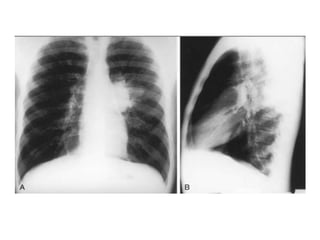

Radiological diagnosis

Chest X-ray

CXR remains an important tool for diagnosis of PTB in children who are sputum smear

negative or who cannot produce sputum

The following abnormalities on CXR are suggestive of Tb :-

• Enlarged hilar lymph nodes and opacification in the lung tissue.

• Miliary mottling in lung tissue

• Cavitation (tends to occur in older children)

• Pleural or pericardial effusion – though seen on CXR – are forms of extra

pulmonary TB that tend to occur in older children

• The finding of marked abnormality on CXR in a child with no signs of respiratory

distress (no fast breathing or chest indrawing) is supportive of TB

Primary Tuberculosis on CXR

1.GangliopulmonaryTB ( Characterized by the presence of

mediastinal and/ or hilar lymphadenopathy and

parenchymal abnormalities, the Ghonfocus

2.TuberculousPleuritis

3.MiliaryTB

4.Tracheobronchial TB

Radiological diagnosis Chest X-ray CXRremains an important tool for diagnosis of PTB in children who are sputum smear negative or who cannot produce sputum The following abnormalities on CXR are suggestive of Tb :- • Enlarged hilar lymph nodes and opacification in the lung tissue. • Miliary mottling in lung tissue • Cavitation (tends to occur in older children) • Pleural or pericardial effusion – though seen on CXR – are forms of extra pulmonary TB that tend to occur in older children • The finding of marked abnormality on CXR in a child with no signs of respiratory distress (no fast breathing or chest indrawing) is supportive of TB

Primary Tuberculosis onCXR 1.GangliopulmonaryTB ( Characterized by the presence of mediastinal and/ or hilar lymphadenopathy and parenchymal abnormalities, the Ghonfocus 2.TuberculousPleuritis 3.MiliaryTB 4.Tracheobronchial TB